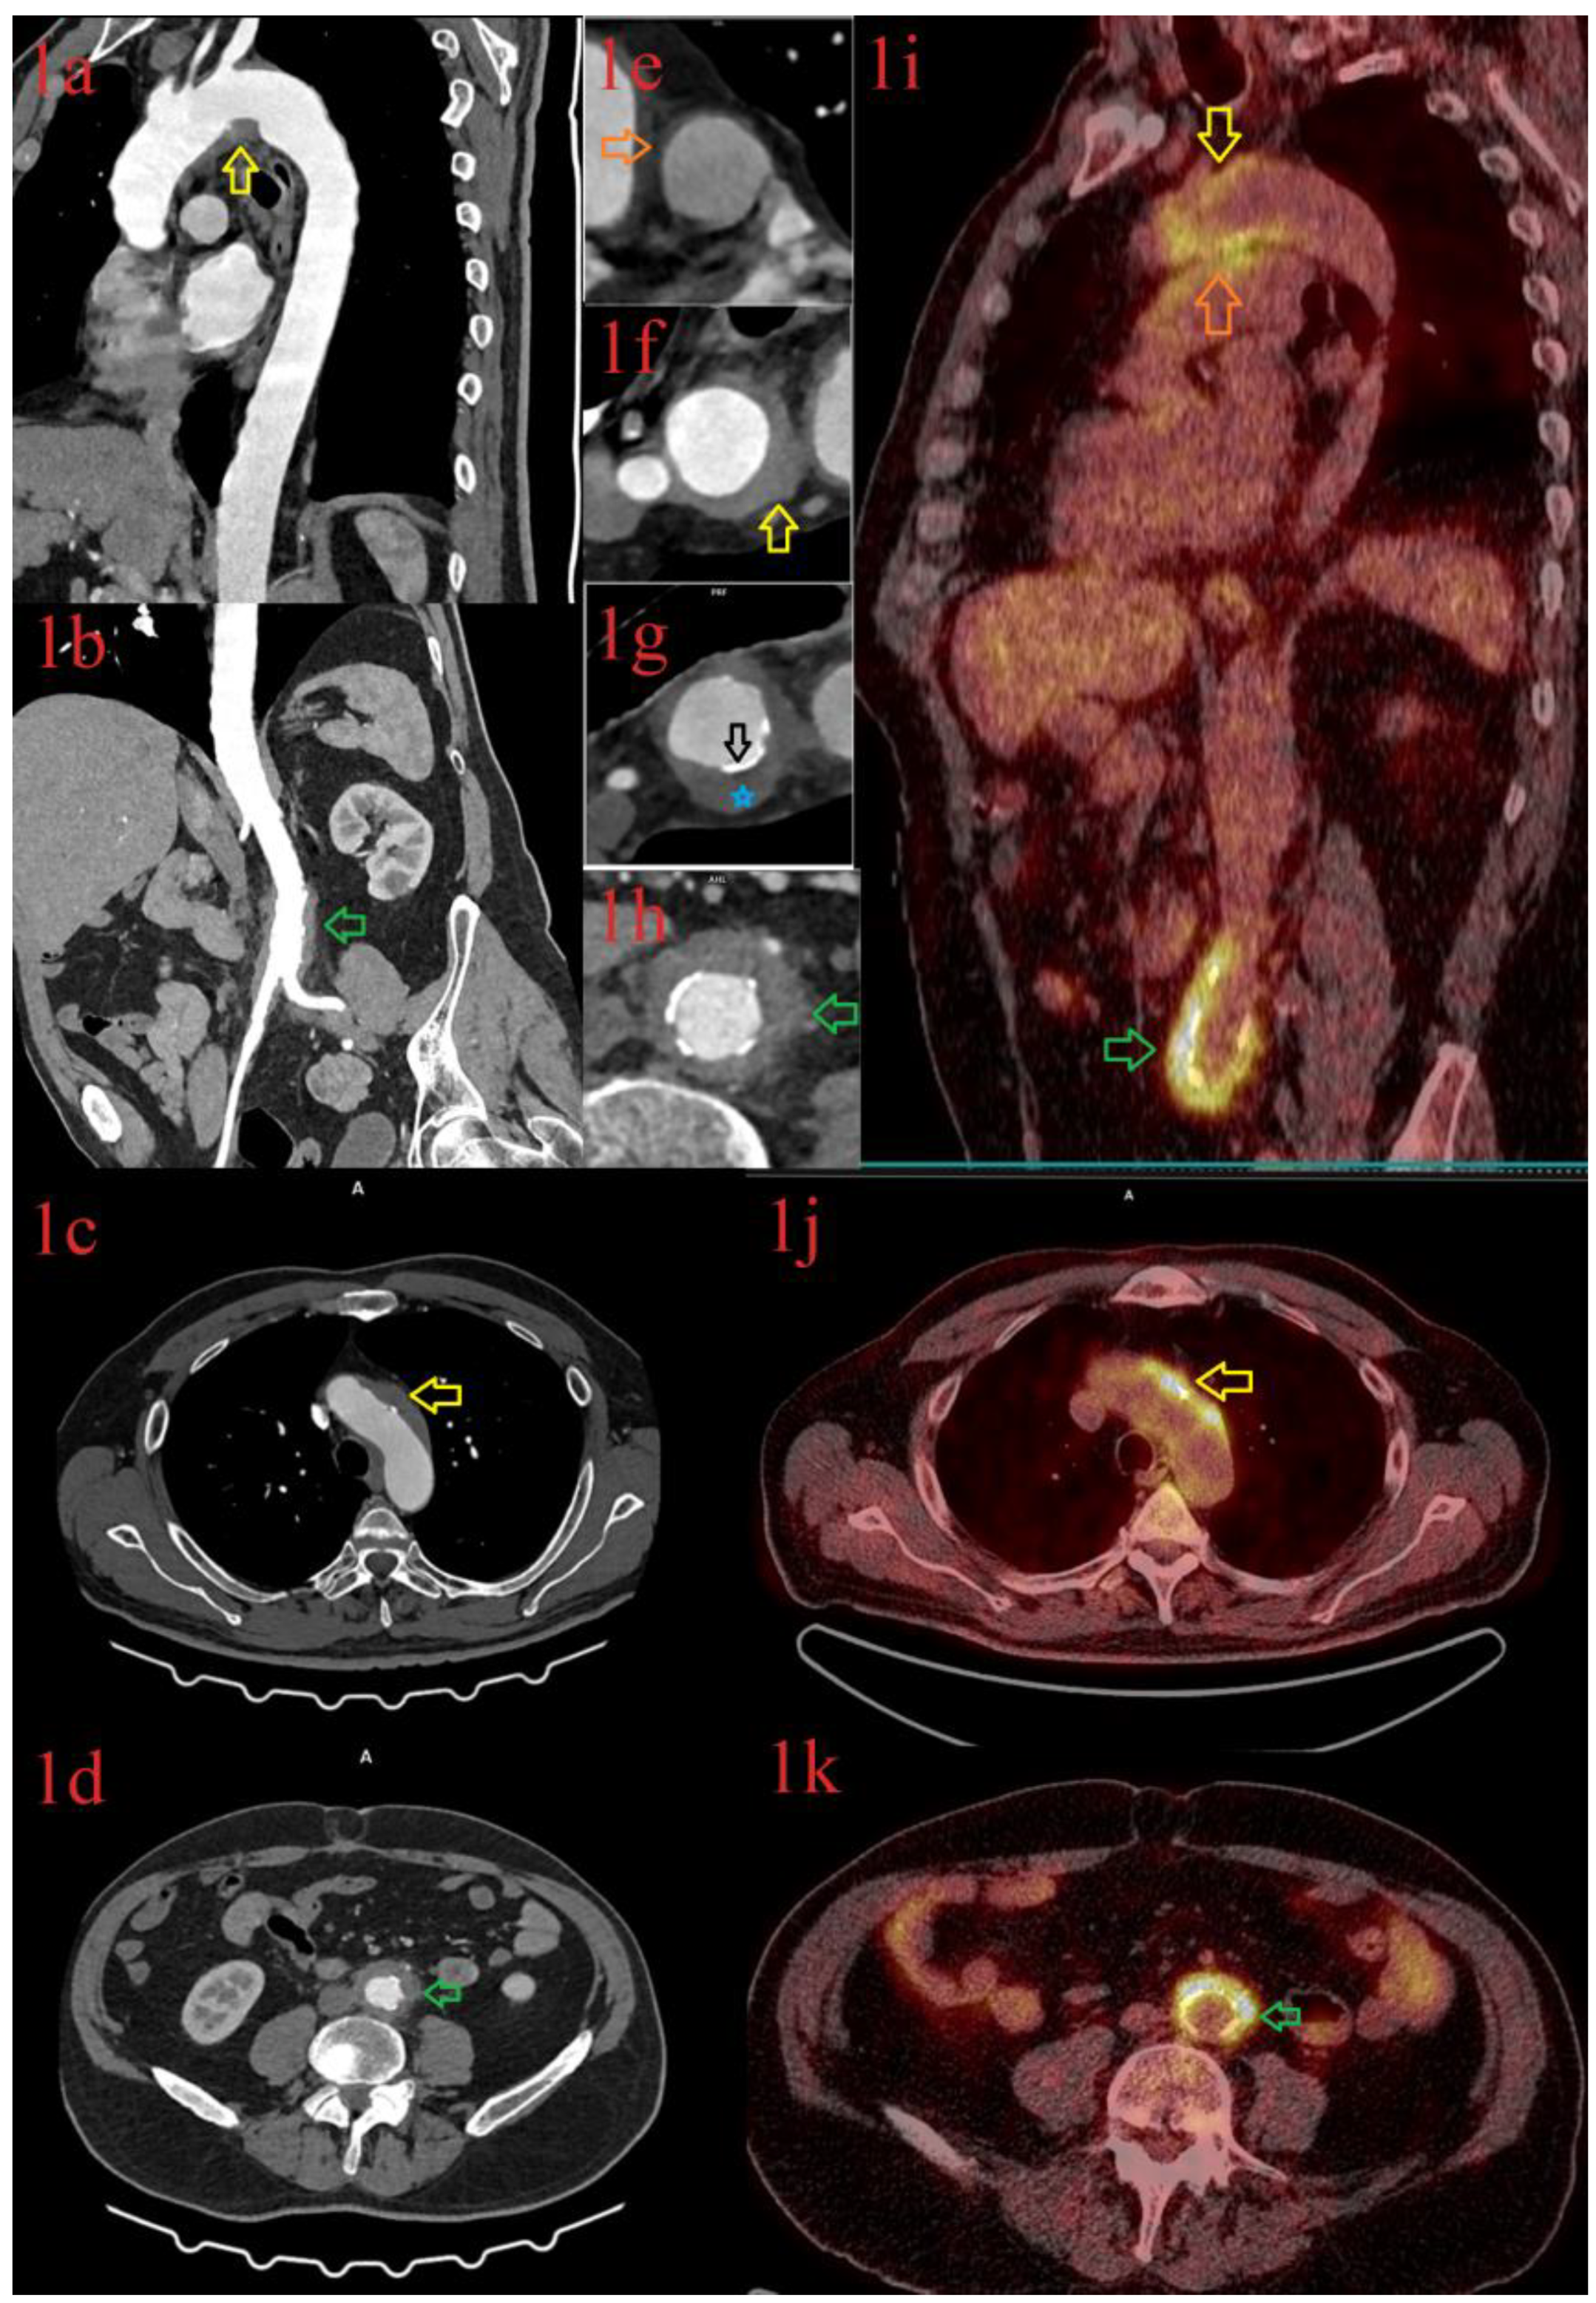

3.1.2. Patient 2